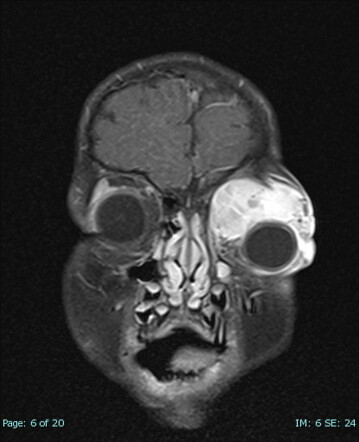

Rhabdomyosarcoma (orbit) | Radiology Reference Article | Radiopaedia.org

radiopaedia.org

radiopaedia.org

Rhabdomyosarcoma - American Academy Of Ophthalmology

rhabdomyosarcoma

Image | Radiopaedia.org

radiopaedia.org

radiopaedia.org

rhabdomyosarcoma mri radiopaedia ct